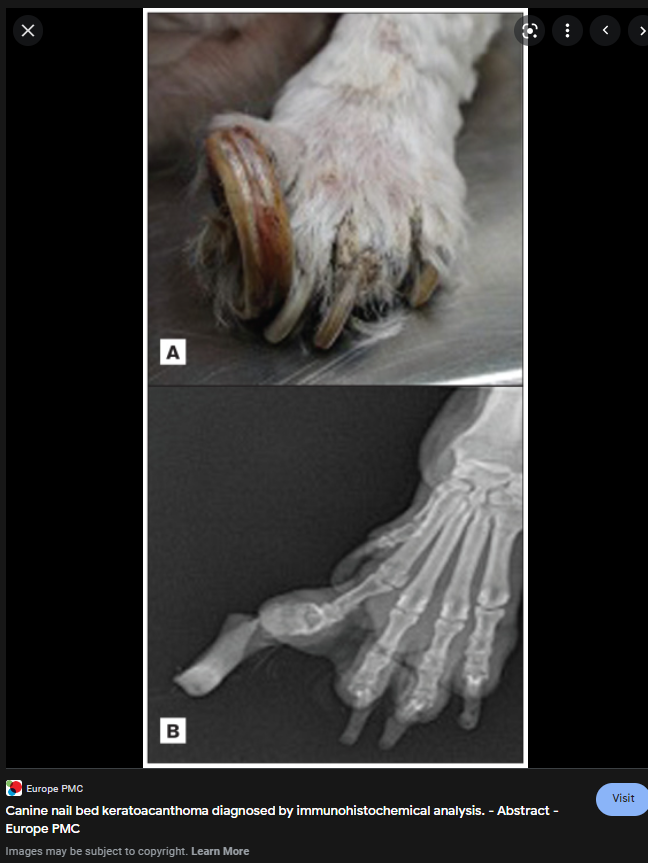

아직 논문이 열리지 않는 최신 지견이라 구글 이미지를 둘러보면

이정도의 영상이 나온다.

이 종양 자체가 양성 종양임에도 불구하고 골 융해를 동반하기 때문에 기능적인 부분에서는 악성형의 증상을 보인다고 할 수 있을 듯 하며

squamous cell calcinoma , synovial cell sarcoma, osteosarcoma와 감별이 필요한 질환이기도 함

양성 종양이기 때문에 원격전이가 일어나지 않기에 발가락 절단만으로도 완치되는 타입의 종양이나

골융해가 있어 osteosarcoma로 단정하여 수술을 보류하지 않아야 할듯, 결국 FNA 나 조직 검사를 해보고 판단하는게 옳지 외견과 방사선 검사 결과만으로 판단해서는 안될 듯 하다.